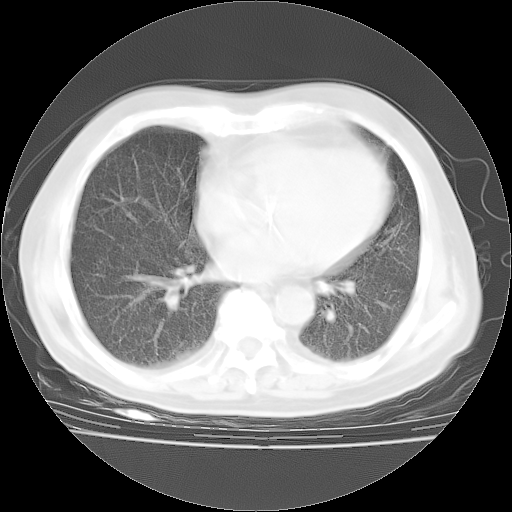

4月28日肺部CT

1、108#的是4月14日的胸部CT(发此贴时还没看着28日的CT)。14日的胸部CT其实已经出现改变(如108#所述),个人认为28日的胸部CT除纵膈窗疑似有双侧胸膜增厚或少量胸积液(可行胸部B超明确)外,与4月14日对照病变有所加重;2、已经给予“异烟肼、利福平、乙胺丁醇”抗痨治疗?如果是,甲强龙80mg可缓慢减量;如果环磷酰胺已停用,暂不使用;3、中性粒细胞92%,明显升高,目前体温情况?注意合并细菌感染可能,使用左氧氟沙星情况下,是否联用B-内酰胺类抗菌药物?另外是查免疫全套非风湿全套。

今请临免主任会诊后认为:4月14日胸部CT已有双下肺间质性改变。患者病情复发多系激素减量过快不正规所致。目前甲强龙80mg/日,一周后酌情开始减量,不易过快。环磷酰胺若已停用,暂不使用。他同意目前抗菌药物使用,但应考虑是否加用B-内酰胺类抗菌药物(中性细胞明显增高);2、结核复发目前依据不足;3、若免疫全套各项指标正常,考虑多系特发性肺间质炎可能大。4、加强支持,并注意保护胃黏膜。